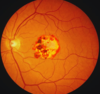

what is the histopathological change seen in diabetic nephropathy

what is the finding